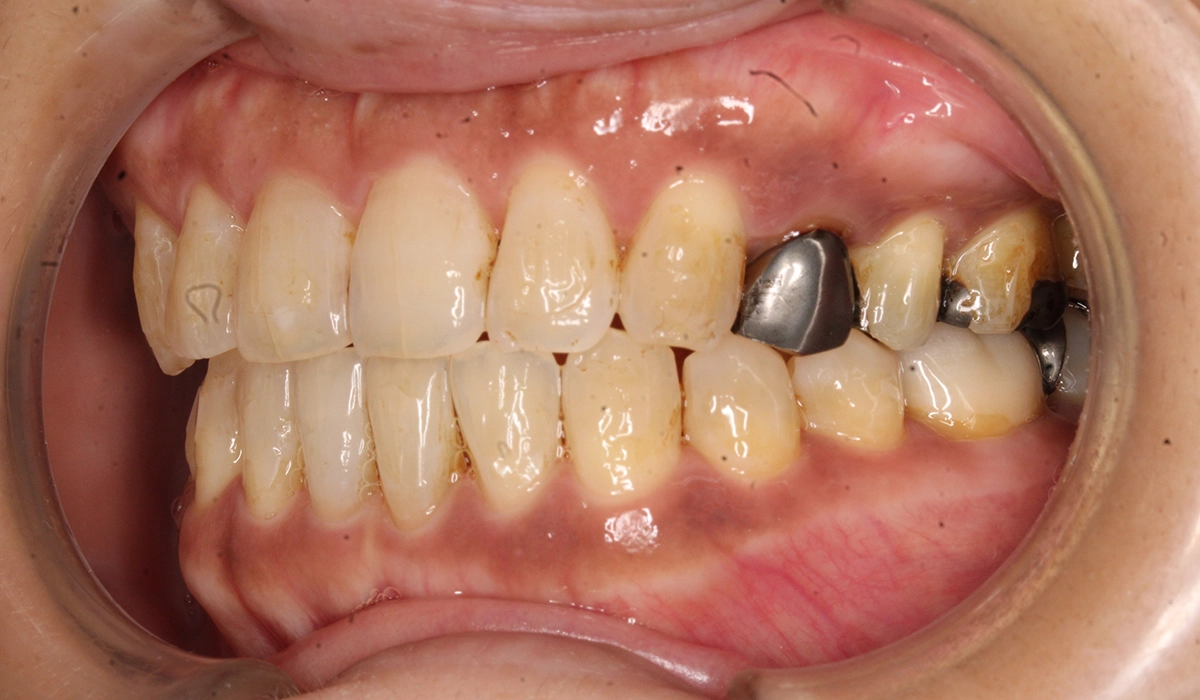

術前:右側